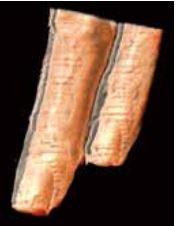

Пальці

На Рис.4 показані зображення нормального пальця. Кровоносні судини, кістки і нігті можна чітко розпізнати за допомогою Smart Sensor 3D (рис. 4а). Shadow Glass також виявився корисним в ортопедичних обстеженнях, наприклад, для візуалізації переломів. Зображення Shadow Glass можуть бути клінічно кориснішими, ніж звичайні зображення, оскільки на одному зображенні можна отримати більше інформації.

Крім того, використання вигнутої С-площини, створеної OmniView (рис. 4б), дозволяє зобразити кровоносні судини в пальцях безперервно. Таким чином, цілісність кровоносних судин можна оцінити, використовуючи як 3D Shadow Glass (рис. 4в, г), так і 2D вигнуту С-площину. Планується, що ці зображення виявляться корисними в широкому спектрі клінічних досліджень, таких як мікрохірургія.

a) Багатоплощинна реконструкція (MPR) та яскравість

б) Вигнута С-площина (OmniView)

в) Shadow Glass: Долоня

г) Shadow Glass: Тильна

Рисунок 4. Нормальні пальці з використанням Smart Sensor 3D